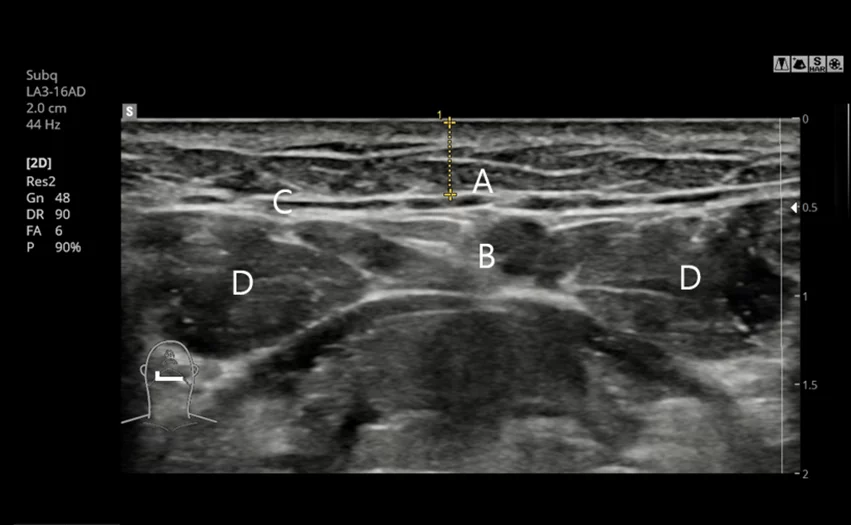

5. การวินิจฉัยเฉพาะบุคคลด้วย CT และอัลตราซาวนด์ก่อนการผ่าตัด

วิเคราะห์ตำแหน่งและขนาดของต่อมน้ำลายอย่างละเอียดด้วยการสแกน CT และการตรวจอัลตราซาวนด์

และหากจำเป็น จะทำการผ่าตัดต่อมน้ำลายออกอย่างประณีตเพื่อความเหมาะสมในแต่ละบุคคล